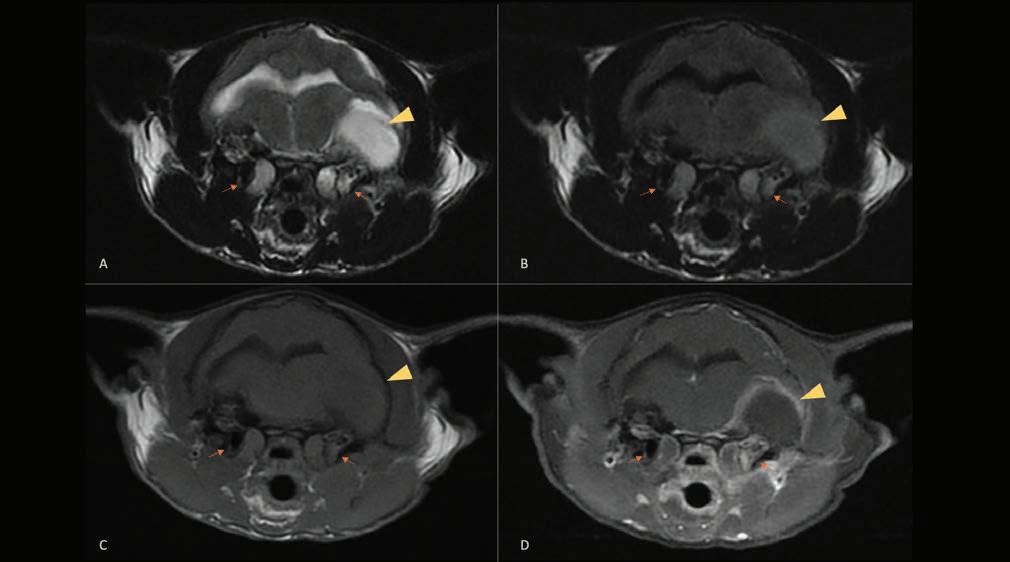

Tras rasurar y desinfectar la EPD, se realizó un bloqueo ecoguiado de los nervios ciático (Fig. 3A) y safeno (Fig. 3B) en el fémur medio,6 con bupivacaína 0,5 % (Bupivacaina 5 mg/ml, B Braun, Rubí (Barcelona), España; 0,1 ml/kg/nervio) y dexmedetomidina (1 μg/kg/nervio). Para ello se utilizó una sonda lineal multifrecuencia 3-13 MHz (MyLab Gamma, Esaote, Florencia, Italia) y agujas sonovisibles (Ultraplex® 360 x 10 mm, 30º, BBraun, Melsungen, Alemania).